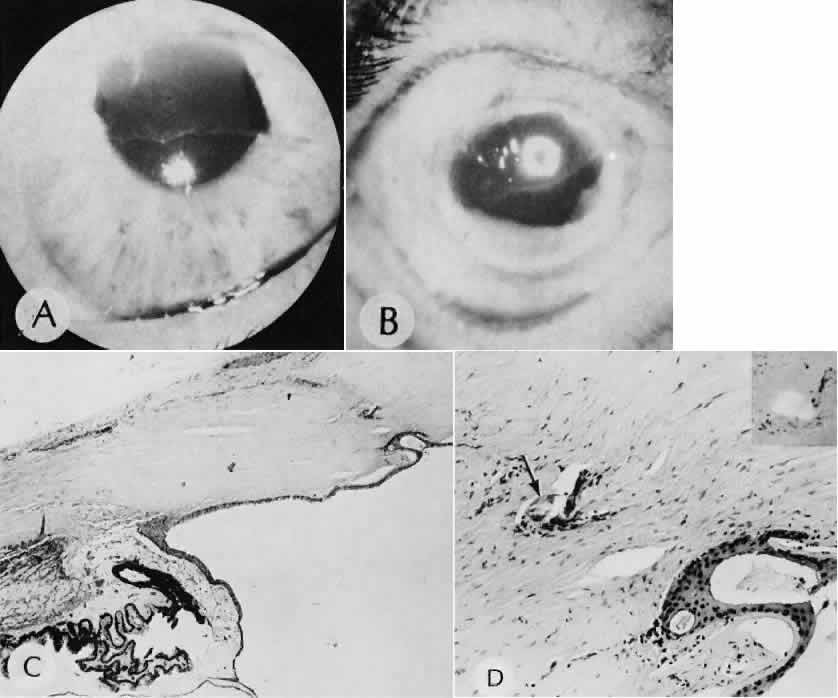

A flat anterior chamber is characterized by anterior displacement of the iris to near or in actual contact with the posterior surface of the cornea. The most common cause is leakage of aqueous along one of the suture tracks. Prolonged decompression of the anterior chamber increases the risk of synechiae formation and intractable secondary closed-angle glaucoma. Corneal endothelial damage may result in bullous keratopathy. Choroidal edema (choroidal hydrops or detachment) (Fig. 31) may be associated with a flat anterior chamber and may potentiate the condition. The choroidal edema will slow or stop aqueous production by the ciliary body, further delaying reformation of the anterior chamber. The histologic characteristics of choroidal edema consist of spreading of the choroidal tissue in a fanlike configuration and eosinophilic fluid filling the intervening spaces. The edema fluid may be lost in processing, leaving multiple apparently empty spaces.

Fig. 31. A case of choroidal detachment. A. By fundus reflex, a large dome-shaped mass can be seen originating from the choroid. The differential diagnosis would include uveal malignant melanoma. In this case, the clinical findings were due to choroidal detachment from the sclera because of fluid accumulating in the suprachoroidal space following cataract surgery. B. The histologic section from another case of choroidal detachment illustrates the location (arrow) and extent of the detachment. In this case the detachment extends to the region of the ciliary body limited anteriorly by the attachment of the choroid to the scleral spur. The displacement of the ciliary body will result in apparent shallowing of the anterior chamber. (Hematoxylin-eosin stain; × 6.)